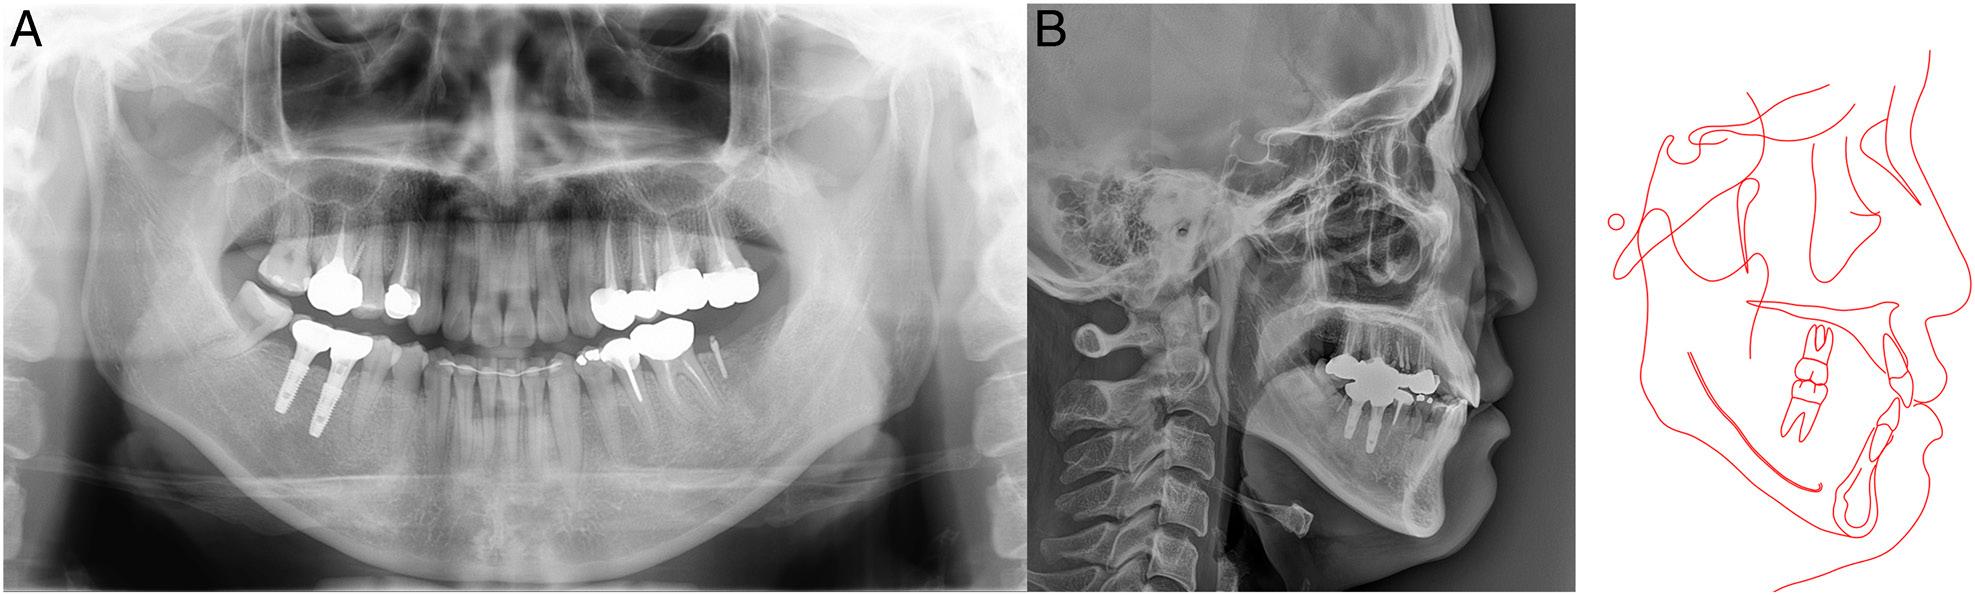

Figure 2.